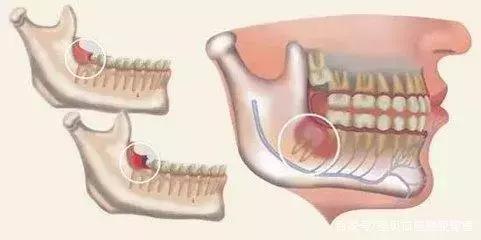

1.由于人类食物的变化而带来咀嚼器官的退化,下颌骨有逐渐缩小的现象,因而造成牙列与颌骨不协调,智齿萌生的位置不足,成为智齿阻生的原因。

3.临床上智齿部分萌出,也是伴发智齿冠周炎的直接原因。智齿在萌生过程中,冠部往往被牙龈瓣覆盖,与牙冠之间形成较深的盲袋,食物及细菌极易嵌塞于盲袋内,一般很难通过漱口和刷牙被清理干净;加之口腔内有非常适宜的温度和湿度,致成为细菌繁殖的温床。

4.由于咀嚼食物和下颌智齿正在萌出过程中,使覆盖于智齿周围的龈瓣可同时受两个方向的机械压力,致经常处于受损伤的状态;龈粘膜易发生糜烂和溃疡,从而降低了局部的抵抗力,细菌可乘隙侵入,从而引起冠周炎的急性发作。

1、 由于萌出不全,后侧的牙龈覆盖,其部分牙冠形成冠周袋积存食物和细菌,可以造成局部软组织经常发炎,疼痛难忍,甚至导致张口受限而进食困难。

4、 会影响其他牙齿龋坏:阻生智齿能使第二磨牙龋坏。向前倾斜的智齿,其牙冠顶在前牙的颈部,这两颗牙之间形成一个滞留区,由于食物残渣的滞留,得不到正常清洁,细菌繁殖产酸,腐蚀牙齿,造成第二磨牙牙颈容易发生龋齿,往往就诊时已不能保留,需要拔除。